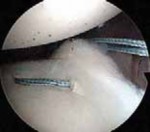

Anchor Placement and Capsulolabral Plication

With the glenoid prepared and the tissue mobilized, fixation begins at the most inferior aspect of the lesion, typically at the 5:30 or 6 o'clock position. Modern fixation relies on either biocomposite or all-suture anchors, typically 1.5 mm to 2.9 mm in diameter. The drill guide is introduced through the anteroinferior portal, and the anchor is deployed on the articular margin (1-2 mm onto the articular cartilage face) to recreate the anatomical labral bumper. The trajectory of the drill is paramount; it must be directed slightly medially to avoid penetrating the articular surface of the glenoid vault.